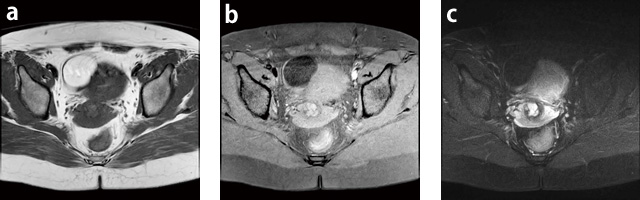

症例1:右卵巣delmoid cyst

子宮がん検診の超音波で指摘され,MRI精査を施行。

最大5cm弱の単房性の脂肪性分の腫瘤を認める。

a:T1WI,AX,FOV:250mm,TR/TE:400/10,FA:90°,スライス厚:7mm

b:T1WI,AX,fatsat,FOV:250mm,TR/TE:580/10,FA:90°,スライス厚:7mm

c:T2WI,AX,fatsat,Rader,FOV:250mm,TR/TE:2500/80,FA:90°,スライス厚:7mm